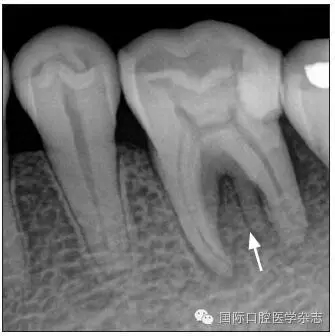

患牙被診斷為根尖周炎,鹽酸甲哌卡因/腎上腺素注射液(斯康杜尼)麻醉后,橡皮障隔濕,開髓,找到3個(gè)根管口。根尖片可見牙槽骨內(nèi)有一個(gè)根樣影像(圖4),故再次尋找根管口,但未找到。

圖 4 根樣釉珠

Fig 4 Root-like enamel pearl